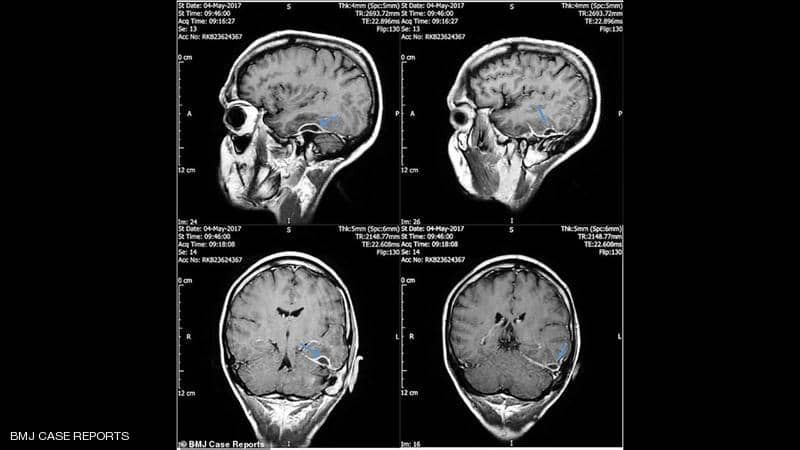

ففي المستشفى، اكتشف الأطباء أن المشكلة “باتت” أعمق مما كان يعتقد وأنها توجد داخل جمجمته.

وعندها تبين لهم أن قنوات الأذن عنده مصابة بالتهاب حاد مع وجود “أوساخ عالقة” سببتها قطعة قطن.

وبحسب الأطباء فإن الالتهاب أصاب الخلايا داخل الجمجمة، ولم يصل إلى خلايا الدماغ.